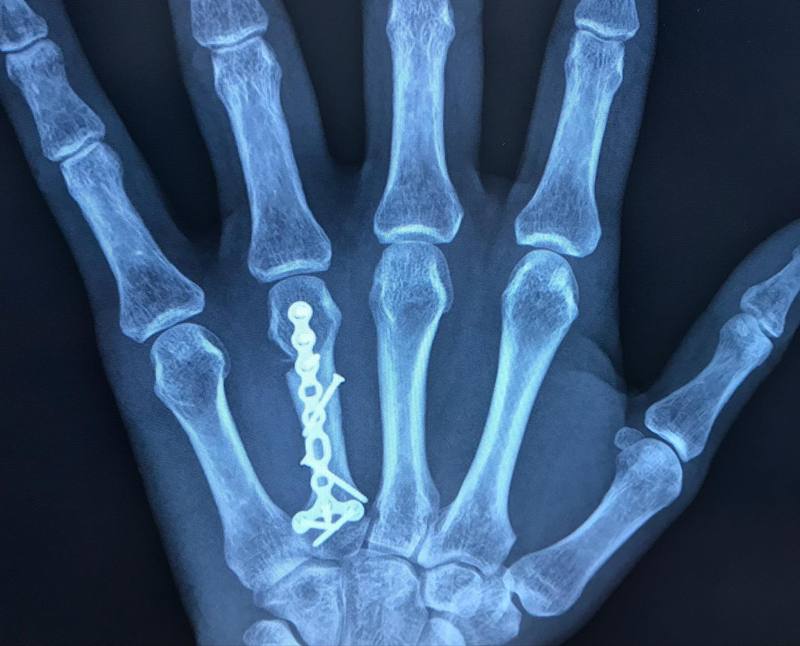

【左環指中手骨骨折のリハビリ順調】

左手の機能も戻りつつあり、日常動作にはほぼ支障はなくなりました。